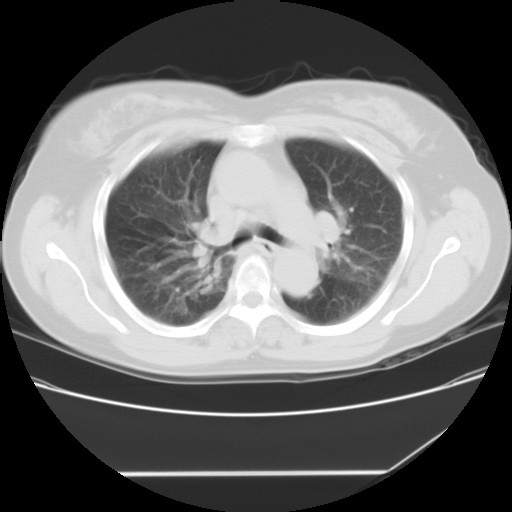

间质性肺炎,有纤维化趋势。

1)慢性支气管炎并肺部感染、肺气肿。2)肺间质纤维化。

间质性肺炎,左下肺机化性肺炎。